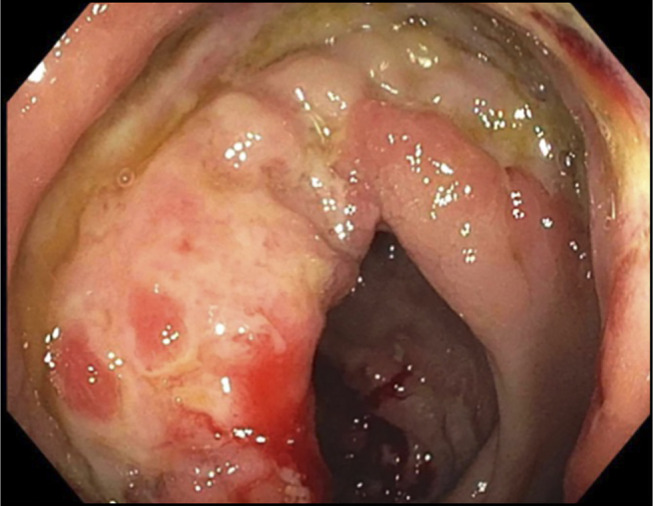

Gastrointestinal tuberculosis (GI TB) is an uncommon sequela of extrapulmonary TB, occurring in 1%-3% of TB cases worldwide. In the United States, many cases are seen in migrant populations or in immunocompromised individuals. The classic presentation of GI TB is nonspecific abdominal pain, and is not typically associated with significant, life-threatening bleeding. We present a case of GI TB complicated by severe lower GI bleed requiring vasopressor support in a newly emigrated patient with previously undiagnosed HIV/AIDS.